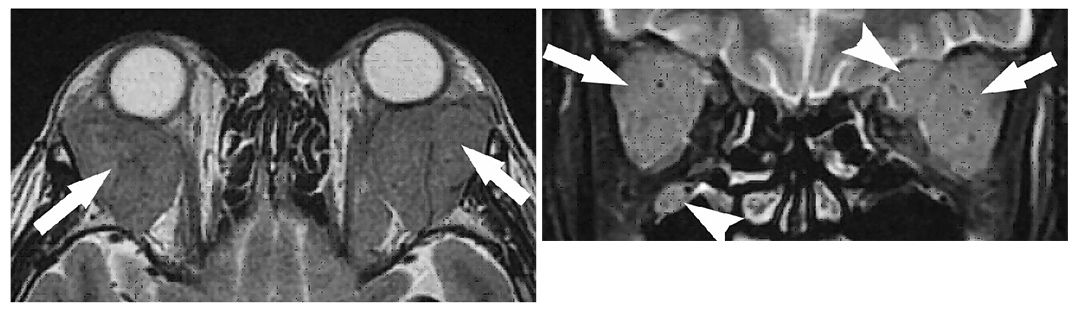

IgG4関連眼疾患の50歳代女性。両側の眼瞼膨張、眼球突出を呈し、MRIでは両側の涙腺腫大(矢印)と三叉神経腫大(矢頭)がみられる。